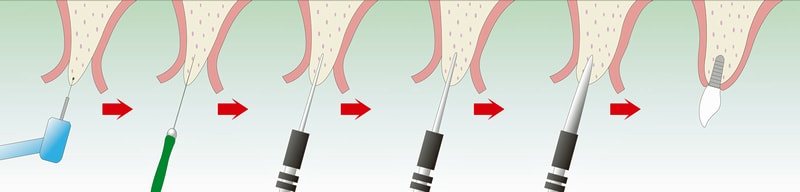

OAM(大口式)インプラントシステムを併用

OAMはドリルを使わず、インプラントを埋入する方法です。

骨をほとんど削らずに済むため、患者さんの身体的負担が少ないのが特徴です。

OAM(大口式)インプラントシステムを併用

OAMはドリルを使わず、インプラントを埋入する方法です。

骨をほとんど削らずに済むため、患者さんの身体的負担が少ないのが特徴です。